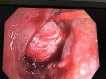

This is a case of a woman with massive hemoptysis, associated with a pulmonary artery pseudoaneurysm, and a fistula between the right pulmonary artery and bronchus intermedius. Bronchoscopic evaluation revealed an endobronchial mass in the right bronchus intermedius, suspicious for a tumor. Upon biopsy of the mass, massive bleeding occurred. The right lung was surgically resected. No specific etiology for the fistula was identified on pathologic examination. To our knowledge, this is the first report of a pulmonary artery-bronchial fistula presenting without typically known predisposing factors.